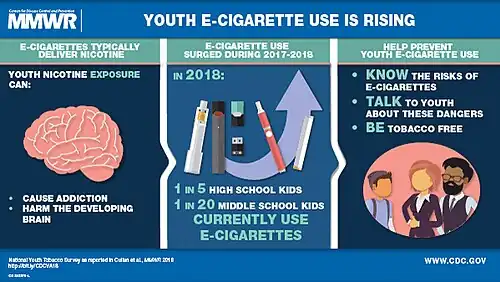

E-cigarettes use by children and adolescents may result in nicotine addiction.[73]: C [74]: A Following the possibility of nicotine addiction via e-cigarettes, there is concern that children may start smoking cigarettes.[75] Adolescents are likely to underestimate nicotine's addictiveness.[76] Vulnerability to the brain-modifying effects of nicotine, along with youthful experimentation with e-cigarettes, could lead to a lifelong addiction.[77] A long-term nicotine addiction from using a vape may result in using other tobacco products.[78]

The majority of addiction to nicotine starts during youth and young adulthood.[79] Adolescents are more likely to become nicotine dependent than adults.[80] The adolescent brain seems to be particularly sensitive to neuroplasticity as a result of nicotine.[44] Minimal exposure could be enough to produce neuroplastic alterations in the very sensitive adolescent brain.[44] Exposure to nicotine during adolescence may increase vulnerability to getting addicted to cocaine and other drugs.[81]

The ability of e-cigarettes to deliver comparable or higher amounts of nicotine compared to traditional cigarettes raises concerns about e-cigarette use generating nicotine dependence among young people.[82] Youth who believe they are vaping without nicotine could still be inhaling nicotine because there are significant differences between declared and true nicotine content.[83]

A 2016 US Surgeon General report concluded that e-cigarette use among young adults and youths is of public health concern.[71] Various organizations,[84] including the International Union Against Tuberculosis and Lung Disease, the American Academy of Pediatrics, the American Cancer Society, the Centers for Disease Control and Prevention, and the US Food and Drug Administration (US FDA), have expressed concern that e-cigarette use could increase the prevalence of nicotine addiction in youth.[85]: IUATLD [86]: AAP [87]: ACS [79]: CDC [88]: US FDA

Adolescents are particularly susceptible to nicotine addiction: the majority (90%) of smokers start before the age of 18, a fact that has been utilized by tobacco companies for decades in their teen-targeted advertising, marketing and even product design.[34] E-cigarette marketing tactics have the possibility to glamorize smoking and enticing children and never smokers, even when such outcomes are unintended.[91] Adolescents may show signs of dependence with even infrequent nicotine use; sustained nicotine exposure leads to upregulation of the receptors in the prefrontal cortex, pathways which are involved in cognitive control, and which are not fully matured until the mid-twenties.[34] Such disruption of neural circuit development may lead to long-term cognitive and behavioral impairment and has been associated with depression and anxiety.[34]

In the US, the unprecedented increase in current (past-month) users from 11.7% of high school students in 2017 to 20.8% in 2018 would imply dependence, if not addiction, given what we know about nicotine and its effects on the adolescent brain.[34] Two recent studies in 2018 utilized validated measures to identify nicotine dependence in e-cigarette using adolescents.[34] Exposure to nicotine from certain types of e-cigarettes may be higher than that from traditional cigarettes.[34] For example, in a study in 2018 of adolescent pod users, their urinary cotinine (a breakdown product used to measure nicotine exposure) levels were higher than levels seen in adolescent cigarette smokers.[34]